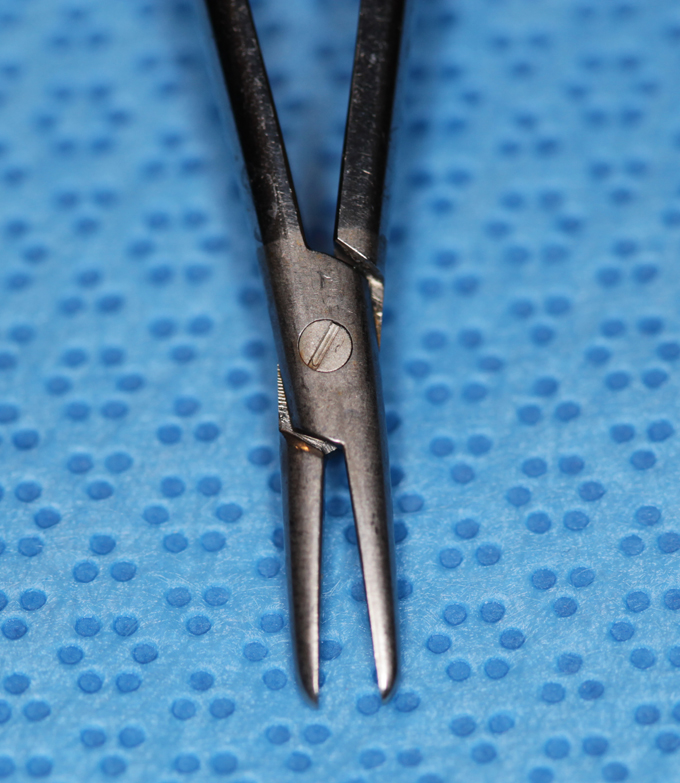

Needleholder, micro titanium micra curved

Needle driver

Catalog: Micra N303W

Typical Use(s): Placing fine suture

Needleholder, micro titanium micra curved (Enlarged)

Needle driver

Catalog: Micra N303W

Typical Use(s): Placing fine suture